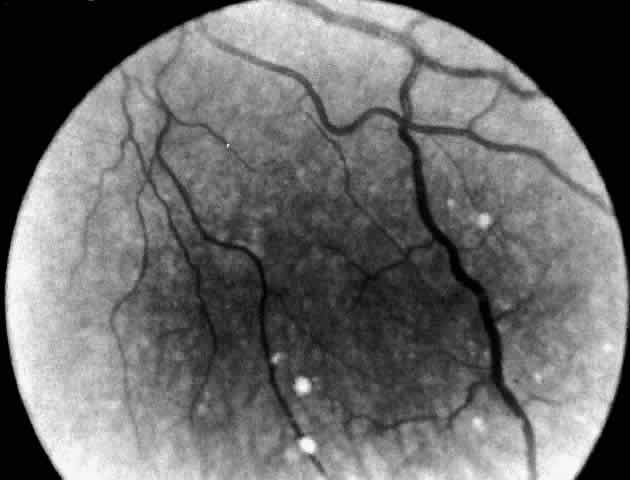

A more widespread opacification of the retina can occur due to involvement of the ganglion cells in the posterior pole. This was observed by Wray4 in a 3½-year-old child with Tay-Sachs disease. The child had black hair and brown eyes, and the cherry-red spot at the macula was brown. The patient was blind, with marked optic atrophy (Fig. 4).

|

A dynamic process of development of the macular cherry-red spot occurs paralleling the infant's progressive neurologic disorder. The cherry-red spot can be observed as early as 2 months of age and is conspicuous at age 4 to 6 months. Loss of visual acuity may occur without noticeable change in the circular halo. But, in time, the ganglion cells atrophy and optic atrophy and loss of the nerve fiber layer occurs. At this stage blindness coincides.

In the final prognosis, infants with Tay-Sachs disease become blind, usually by 18 months of age. The pupils are areflexic to light. In the rare patient noted to have brisk pupillary responses despite blindness, the visual loss may be cortical in origin. At this stage, the visual evoked response (VER) is no longer elicited although the flash electroretinogram (ERG) remains intact.